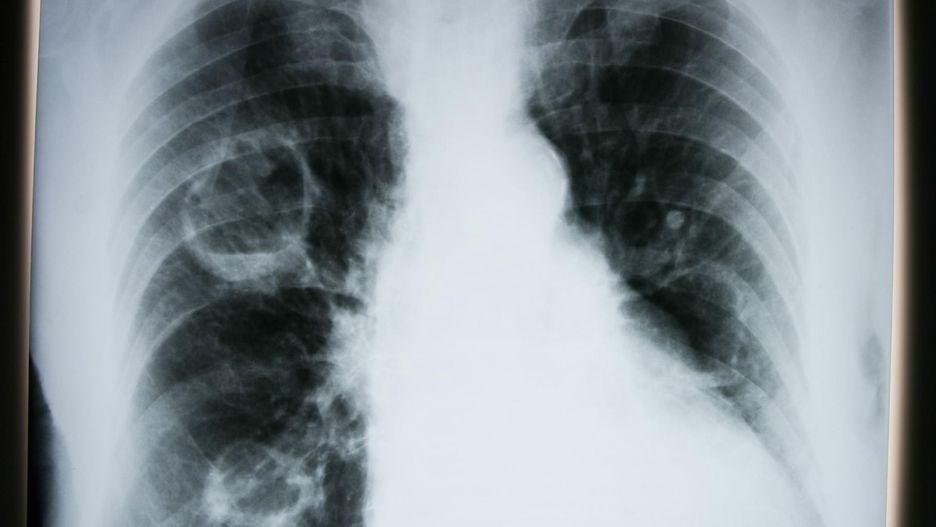

Płuca chorego na COVID-19

Płuca chorego na COVID-19 © Cardiothoracic Imaging

- Następnie dochodzi do reakcji w płucach polegającej na zwiększeniu objętości komórek, które wyściełają pęcherzyki płucne i pogrubieniu ich ścian, następuje też poszerzenie naczyń krwionośnych. Pojawienie się płynu w pęcherzykach płucnych powoduje wyłączenie tych obszarów z oddychania - tłumaczy prof. Mróz.

W ciągu pierwszych pięciu dni zmiany obejmują niewielkie obszary. Ekspert przyznaje, że najczęściej w pierwszej kolejności wirus atakuje prawe płuco, z czasem wysięki rozszerzają się na obie części organu. Wysięk doprowadza do duszności.